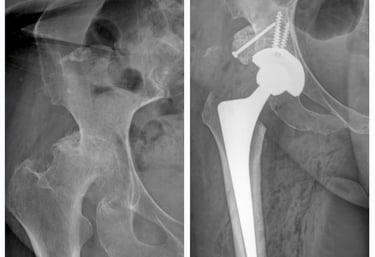

Displasia del desarrollo de cadera: es una alteración en la formación de la articulación de la cadera que está presente desde el nacimiento. Puede provocar que la cabeza del fémur no encaje bien en el acetábulo (la cavidad de la pelvis), lo que con el tiempo ocasiona dolor, cojera y desgaste temprano de la articulación. Su detección y tratamiento oportuno permiten prevenir complicaciones y preservar la función de la cadera.

Secuelas de displasia de cadera

Cirugía en la que se reemplaza la articulación dañada por una prótesis nueva. Se realiza en casos de desgaste severo, artrosis o lesiones que provocan dolor intenso y limitan la movilidad. El objetivo es devolver la capacidad de caminar, realizar actividades cotidianas sin dolor y mejorar la calidad de vida.

Prótesis de cadera y rodilla